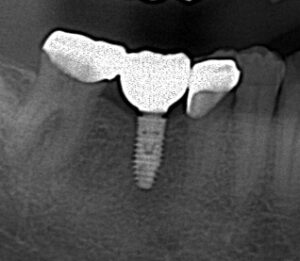

コーヌスデンチャーとは残っている歯に冠のような金属を被せてその上にさらに金属を被せる

2重の冠でできた入れ歯になります。茶筒の原理で固定されるため安定感が高く、審美性や装着感に

優れています。ドイツで開発されたテレスコープデンチャーの一種です。

画像の様なイメージになります。針金を使いませんので

見た目がよくまた維持力も大きくとても良好な義歯となります。